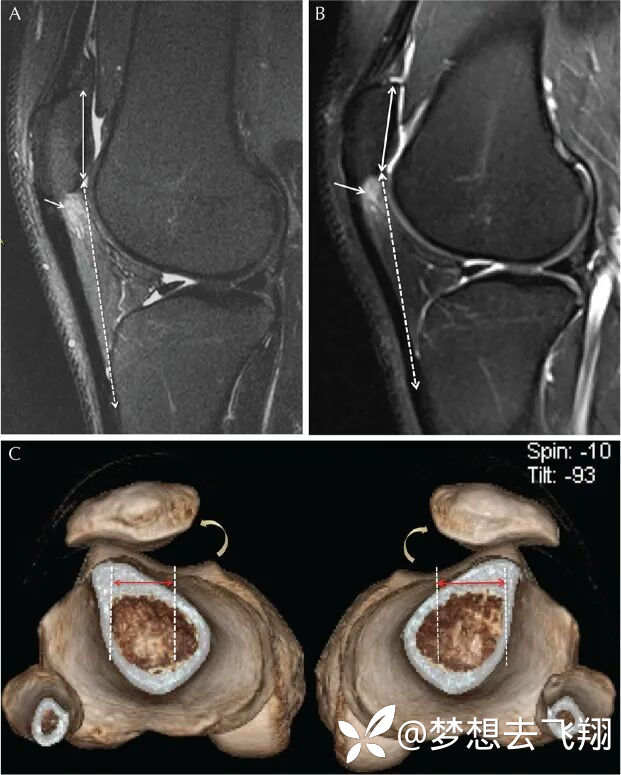

图7:28 岁女性因髌骨发育不良导致双侧膝关节前部疼痛,双侧上外侧髌下脂肪垫信号(箭头)增加,参考2

图8:46 岁女性髌腱外侧和股骨外侧髁之间的Hoffa脂肪垫上外侧存在高信号强度(水肿)(实心箭头)。参考2

图9:40岁单侧进行性右侧性膝痛,临床检查时伴有关节积水症上下楼梯时加重。标准X线片正常。参考7

图9的解释:MRI显示Hoffa脂肪肥大为异质性低信号T1(A),高信号T2为脂肪饱和度(B),钆注射后异质性增强。